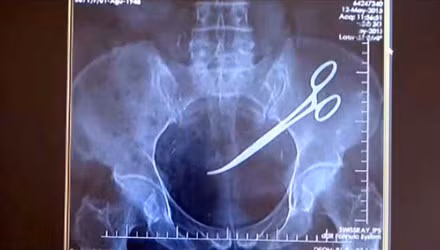

Bỏ quên kéo trong bụng bệnh nhân

Tháng 11/2015, bà Hanim (Thổ Nhĩ Kỳ) phát hiện những cơn đau bụng và dạ dày liên tục. Bà đã đến bác sĩ để thăm khám nhằm xác định nguyên nhân. Qua phim chụp X quang, các bác sĩ nhận thấy có một dị vât ở bụng, gây viêm nhiễm nặng toàn bộ khu vực ổ bụng.

Thấy tình hình khẩn cấp, các bác sĩ đã tiến hành phẫu thuật lấy dị vật ra khỏi bụng bà. Dị vật được xác định là cái kéo phẫu thuật đã bị bỏ lại bên trong.

Được biết, trước đó, bà từng trải qua quá trình phẫu thuật để cắt bỏ ung thư cổ tử cung. Ca phẫu thuật được xem là thành công nhưng về sau những cơn đau ở bụng liên tục xuất hiện. Dù lo lắng nhưng khi nghe bác sĩ nói đó là đau hậu phẫu nên bà không mấy lo lắng.

Sau sự việc trên, bà Hanim đã đệ đơn kiện bệnh viện và đòi bồi thường cho những đau đớn đã phải trải qua suốt 5 năm.